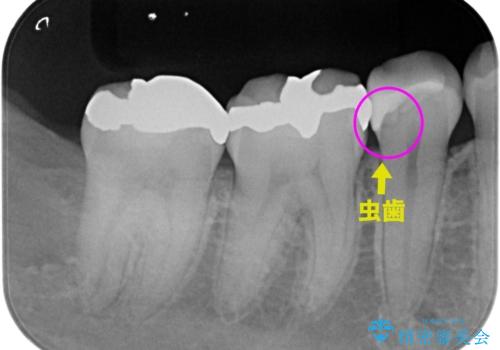

レントゲンで見つかった歯と歯の間の虫歯をセラミックインレーで修復

- 定期検診でレントゲンを撮ったら虫歯(カリエス)があったため、e-maxインレーにて治療しました。